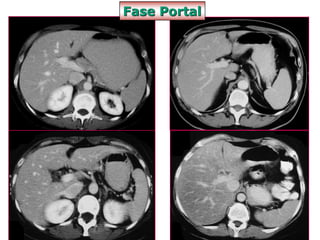

Fase Portal